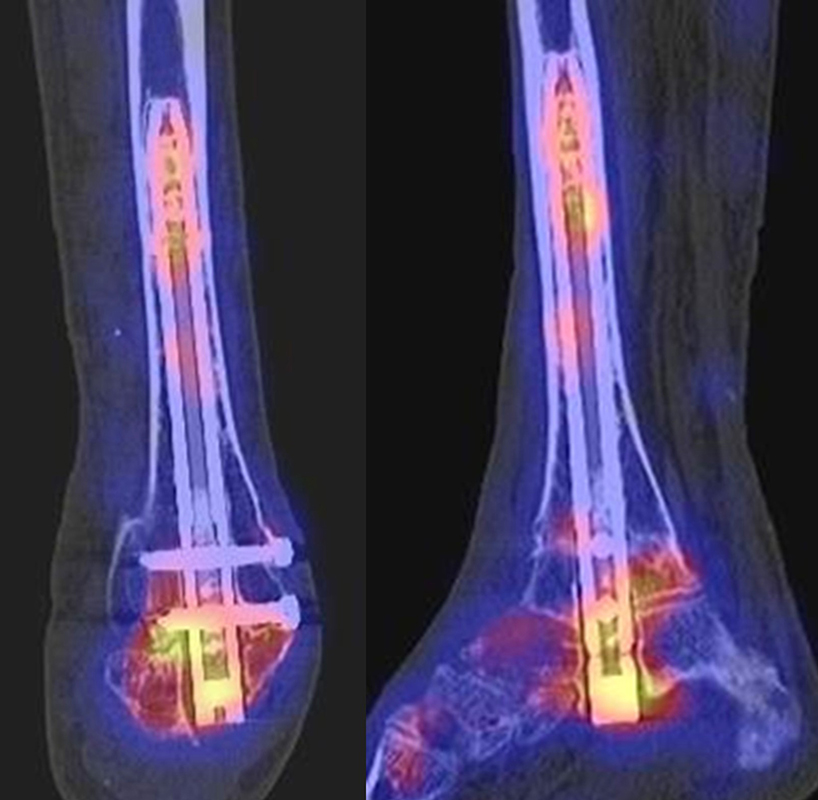

SPECT/CT zur Beurteilung von Arthrodesen

Arthrodesen gehören seit langem zu den Standardverfahren bei Fehlstellungen oder schmerzhaften Arthrosen 4546 (Graves, 2000). Eine zumindest teilweise knöcherne Durchbauung von Arthrodesen sollte in der Regel innerhalb von 6 Monaten nach der OP nachweisbar sein 647. Eine unvollständige oder fehlende Fusion nach Arthrodese kann permanente Schmerzen verursachen, was sich mit der SPECT/CT nachweisen lässt. Abbildung 5.1. zeigt den Fall eines Patienten mit persistierenden Beschwerden 1 Jahr nach calcaneo-cuboidaler Arthrodese, es besteht ein erhöhter Knochenmetabolismus im Bereich der Arthrodese bei teilweise noch abgrenzbarem Gelenkspalt; kein Nachweis von Anschlussarthrosen in den benachbarten Gelenken. Persistierende Beschwerden nach Arthrodese können jedoch auch durch Überlastungen angrenzender Gelenke entstehen, die dann in Arthrosen münden 48. Ein entsprechendes Beispiel ist in Abbildung 5.2. dargestellt, die den Verlauf bei einer Patientin mit Z. n. Arthrodese wegen einer talonavicularen Arthrose zeigen.

Ein weiteres Beispiel für eine im Verlauf entstandene symptomatische Arthrose in den Nachbargelenken zeigen die Abbildungen 5.3.a und b. Bei dem Patienten bestand ein Z. n. subtalarer und talo-navikularer Arthrodese vor 11 Monaten mit Beschwerden beim Abrollen im linken Sprunggelenk mit dem Gefühl „einer Sperre“. Abbildung 5.3.b zeigt die Entwicklung einer anterior betonten hypermetabolen OSG-Arthrose mit Zeichen einer teilweise knöchernen Durchbauung der subtalaren Arthrodese links. Noch keine signifikante Durchbauung der talo-navikularen Arthrodese links. Die Abbildungen 5.4.a bis c zeigen als Erklärung für Schmerzen eine symptomatische Osteochondrale Läsion in der Talusrolle bei knöcherner und reizloser Durchbauung der Arthrodesen 14 Monate nach USG- und TN-Arthrodese.

Der optimale Zeitpunkt einer Evaluation bei Verdacht auf eine symptomatische Arthrodese ist nicht definiert. Im Rahmen einer prospektiven Studie an 30 Patienten mit 31 Sprunggelenksarthrodesen wurden diese prä- und 6 Monate postoperativ mit SPECT/CT und klinisch zusätzlich mit standardisierten Fragebögen (Ankle Osteoarthritis Scale (AOS), 36-item Short Form Survey (SF-36), Physical component score (PCS) and mental component score (MCS)) untersucht 49. Der klinische Erfolg war durch eine Schmerzreduktion unter Belastung definiert (bei 87 %). Radiologisch wurde eine knöcherne Durchbauung von ≥ 50 % nach 6 Monaten als Erfolg definiert (bei 71 %). Szintigraphisch wurde sowohl der Metabolismus um das fusionierte obere Sprunggelenk als auch um die Talonavicular- und Subtalar-Gelenke gemessen. Die Metabolismus um die OSG-Arthrodese war vom präoperativen nicht signifikant verschieden, wobei der Metabolismus um die Talonavicular- und Subtalar-Gelenke signifikant zunahm.

Diese Ergebnisse unterscheiden sich von den zahlreichen präoperativen Studien, die eine hohe Korrelation zwischen SPECT/CT-Metabolismus und klinischen Beschwerden zeigen. Der Grund liegt darin, dass die Szintigraphie sehr sensitiv die Aktivität von Osteoblasten anzeigt und nach 6 Monaten die knöcherne Durchbauung im Sinne einer Normalisierung des Knochenstoffwechsels noch nicht abgeschlossen ist. Unter diesem Aspekt erscheinen 6 Monate zu früh für eine szintigraphische Arthrodesen-Beurteilung.

Der zunehmende Metabolismus in den Talonavicular- und Subtalar-Gelenken ging nicht mit morphologischen Veränderungen als Hinweis auf Anschluss-Arthrosen her, so dass die Autoren diese Befunde als belastungsbedingt bzw. reaktiv nach OP einstuften; wohlgemerkt hatten die Patienten ja weit überwiegend eine deutliche klinische Besserung nach der OSG-Arthrodese erfahren 49.